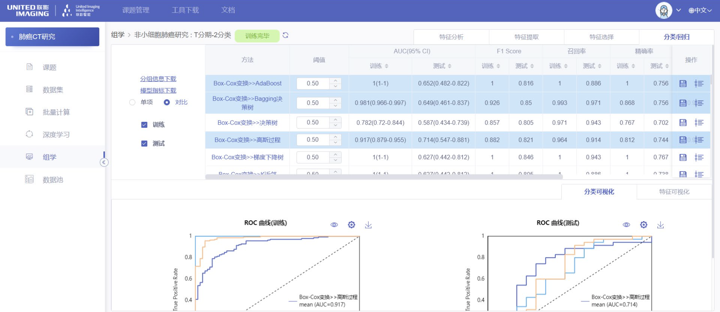

影像组学模块:在组学模块中包含三个子模块:特征提取、特征选择以及机器学习模型的训练。特征提取是在ROI区域提取图像相关的统计特征;特征选择是在特征提取的基础上做相关性分析;机 器学习模型的训练是在特征提取以及特征选择的基础上做相关分类、回归。

最后举一个用该平台发表SCI的论文,感兴趣的可以看一看。